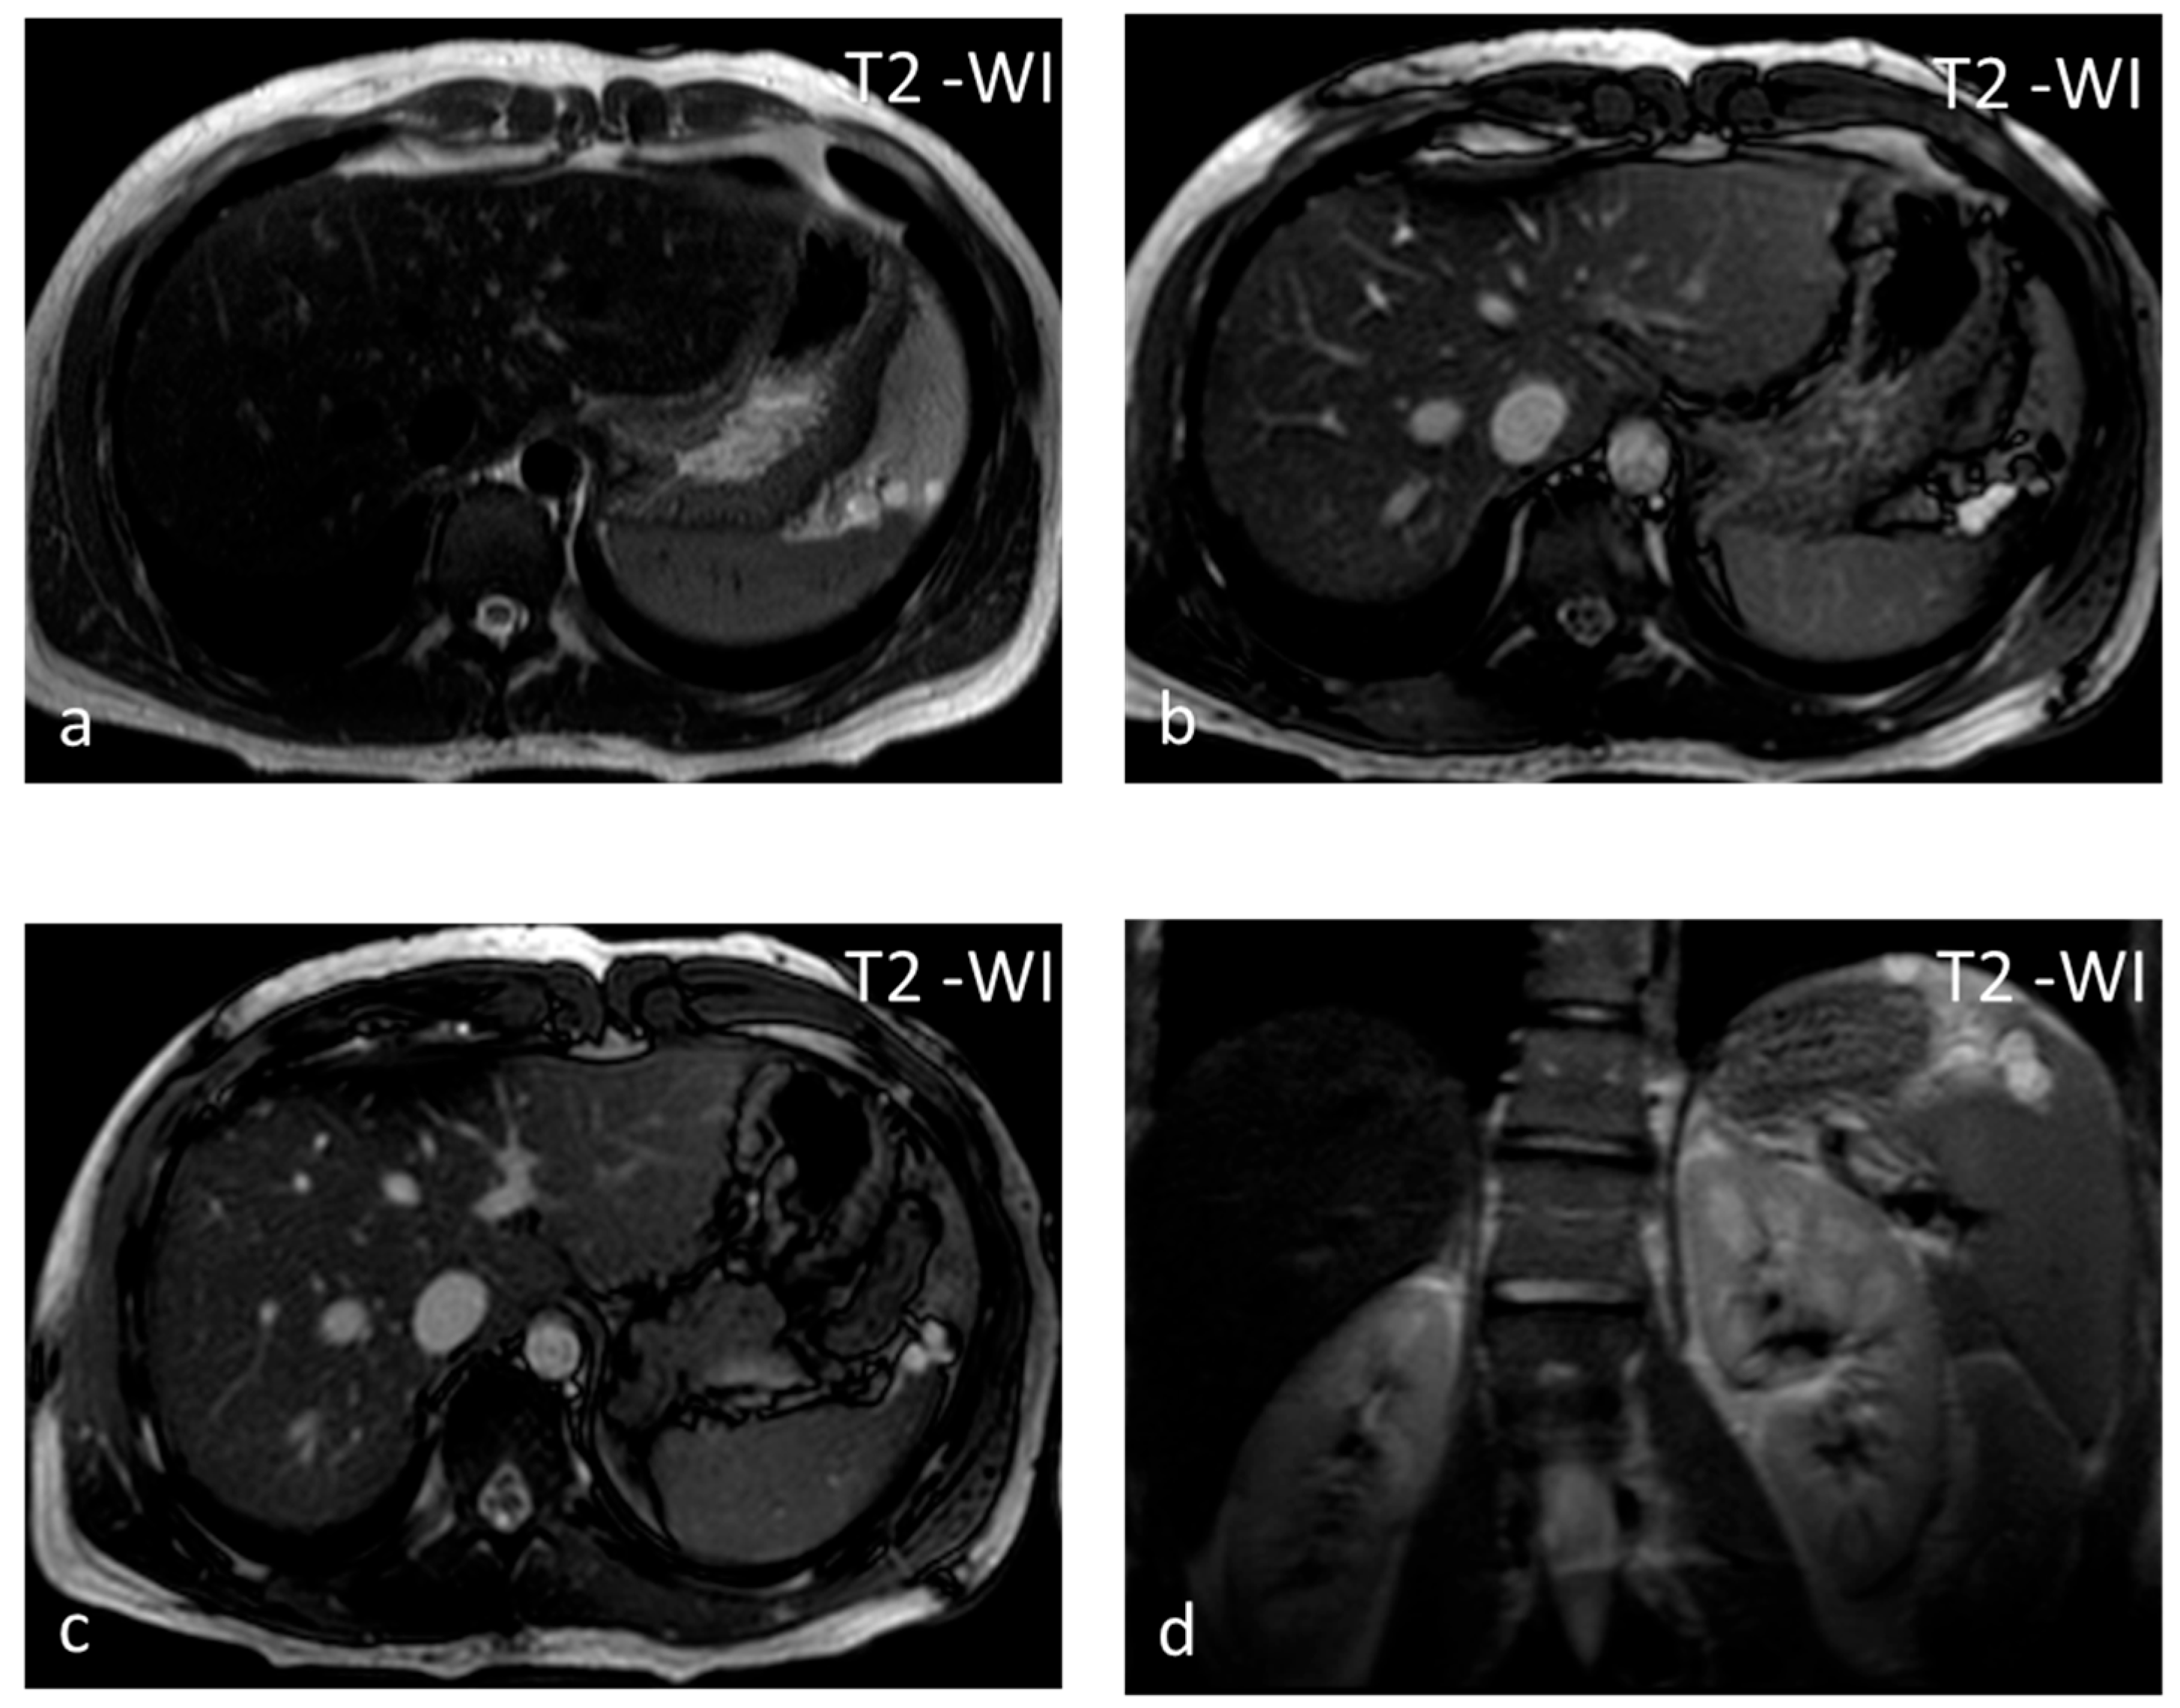

Lymphangioma, a vascular lesion like hemangioma, is a rare benign lesion that is commonly seen in children and exceptional in adults. In 60% of cases, the diagnosis is made before the age of 1 year. Lymphangioma is commonly subcapsular and may have satellite lesions [24]. Similarly to hemangiomas, lymphangiomas can involve the spleen exclusively, or they may be part of generalized angiomatosis, with lymphangiomas or hemangiomas involving several organs in the body [25]. US shows a rounded, well-defined hypoechoic lesion, possibly with internal septations and intralocular echogenic debris [26]. On CT, lymphangiomas appear as single or multiple thin-walled hypodense lesions with no enhancement in a typical subcapsular location [26]. Peripheral wall calcifications can be present. The lesion has typical benign cystic MRI features and may be multiloculated with hypointense thin septa (Figure 3), which may show enhancement. The management of choice for symptomatic, i.e., presenting with left upper quadrant pain and/or splenomegaly, lymphangiomas is splenectomy, as delay in therapeutic intervention can lead to life-threatening complications [24].

Figure 3.

Lymphangiomas. Multiple, subcapsular, hyperintense lesions, one of which appears multiloculated with thin septa, are seen on axial T2-WI images (a–c) and coronal plane T2-WI image (d).